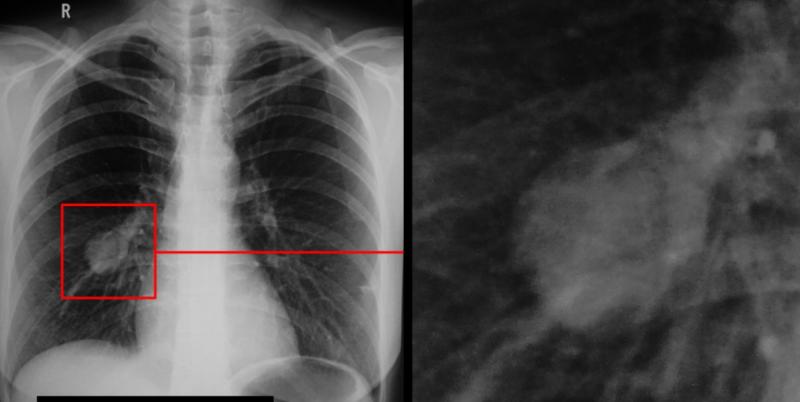

Красноярские медики запатентовали новый метод диагностики рака лёгких

Специалисты Центра ядерной медицины Федерального Сибирского научно-клинического центра ФМБА России разработали и запатентовали инновационный способ диагностики рака лёгких. Новый метод позволит выявлять заболевание на ранних стадиях и обнаруживать даже мельчайшие метастазы.

Как сообщили в ФМБА, технология основана на использовании молекул ДНК и РНК, способных связываться исключительно с опухолевыми клетками. Это обеспечивает высокую точность и минимизирует риск ложных результатов.